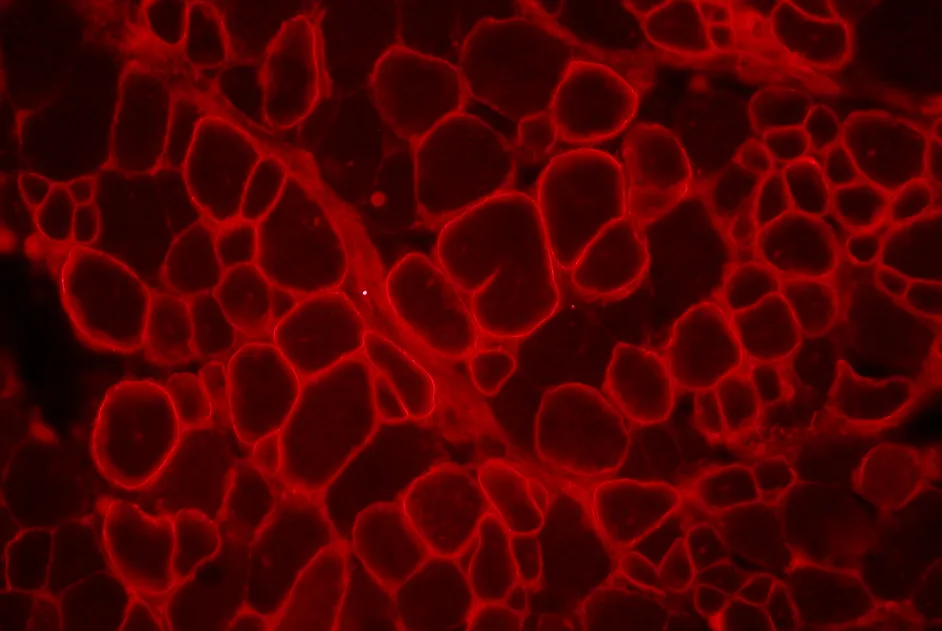

Preuve de concept de l’efficacité du saut d’un pseudo-exon du gène RYR1 pour augmenter l’expression de la protéine RYR1 normale.